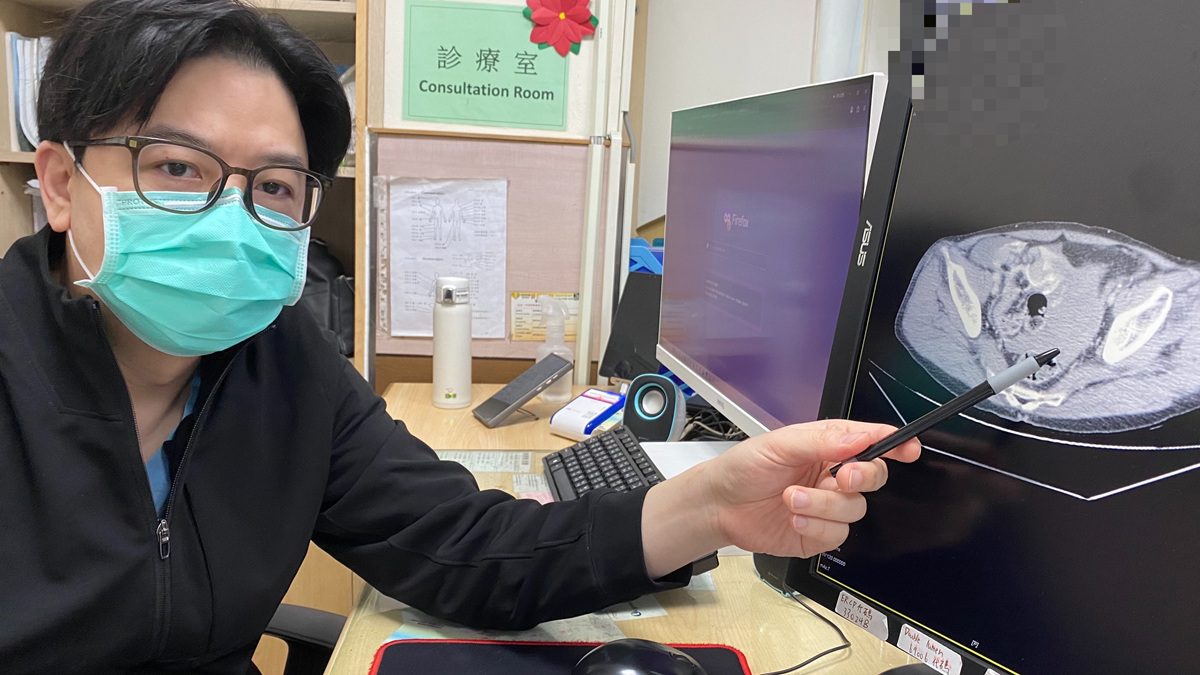

▲王醫師呼籲,看似外傷表淺,仍可能伴隨深層肌肉出血、腸系膜破裂、骨盆損傷或內臟挫傷,延誤治療恐影響生命安全。(圖/員榮醫院提供)

▲王醫師呼籲,看似外傷表淺,仍可能伴隨深層肌肉出血、腸系膜破裂、骨盆損傷或內臟挫傷,延誤治療恐影響生命安全。(圖/員榮醫院提供)